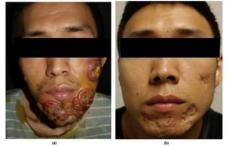

西安交大二附院研究新发现:PRF1突变导致严重皮肤结核感染

西安交大二附院研究新发现:PRF1突变导致严重皮肤结核感染

2023-05-15